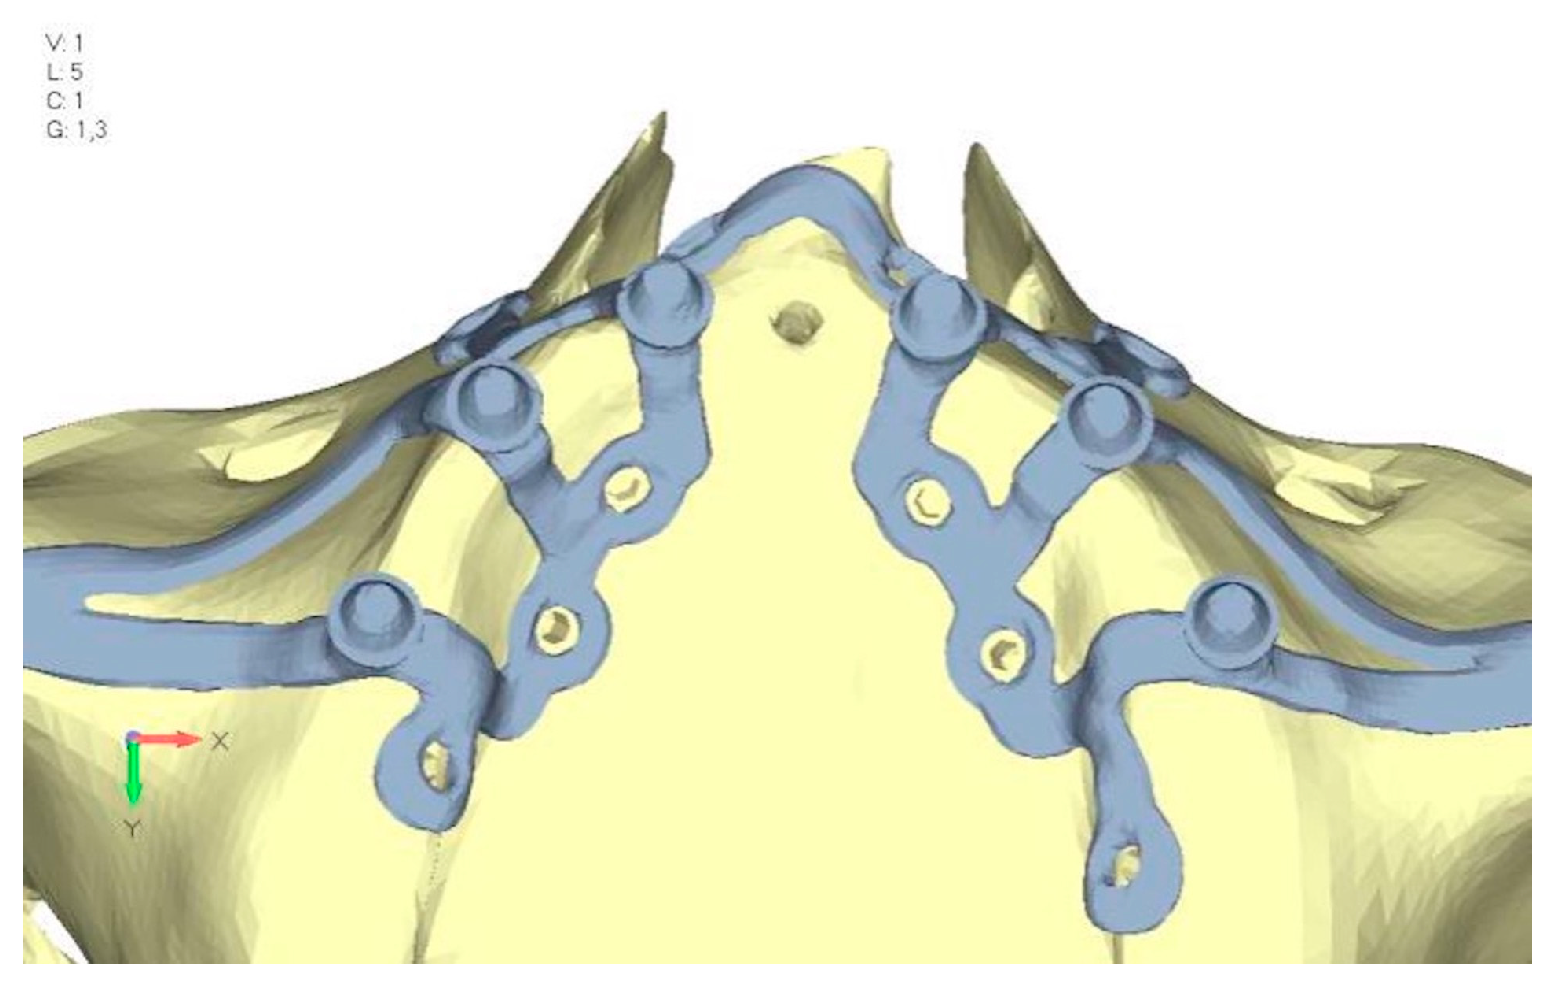

- Model V2. This model serves as an alternative to model V1, as it aims to stabilize the structure posteriorly using screws placed in the vestibular direction rather than the palatal direction (Figure 10). The model displayed similar behavior to V1, leading to the decision to proceed with V1 for further development (Figure 11a,b).